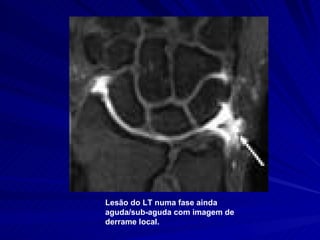

Lesão do LT numa fase ainda aguda/sub-aguda com imagem de derrame local.

Lesão do LTnuma fase ainda aguda/sub-aguda com imagem de derrame local.